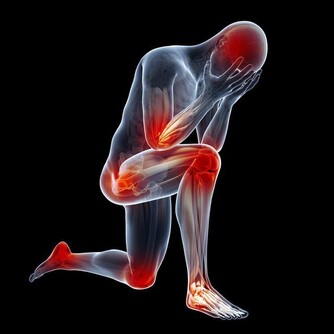

筋脈遍布全身,聯繫帶動骨關節運動,人一老就會彎腰駝背,手上、腳上出現“筋疙瘩”,按上去隱隱作痛,這就是中醫稱作筋結。

筋結對人體循環造成很多不利!人體肌肉組織是由許多平行排列的肌纖維組成,各肌肉外包被筋膜,筋膜分淺層筋膜與深層筋膜,,筋膜下骨骼肌受到肌外膜,肌束膜,肌內膜保護及強化連接,將肌肉分成幾個束狀纖維狀,然因諸多因素如:姿勢不良、運動不足、肌肉缺乏鍛煉、乳酸堆積、工作勞損或撞擊瘀傷、風寒侵入等,使局部氣血循環不好,筋肉成硬塊組織或呈現條索狀,即所謂“筋結現象”。

筋縮就是伸縮範圍減小了,原來能拉一米的筋現在只能拉至半米了。筋縮的“筋”從病理上看,有纖維化、粘連、瘢痕形成、增厚、腫脹,有老百姓所說的“筋疙瘩”形成。這種“筋疙瘩”即筋結。“身有千千結”,這千千結就是我們身上的筋結。

觸摸有筋結的部位,會感覺緊張、僵硬、痙攣、腫脹,會摸到增厚甚至“筋疙瘩”,壓痛明顯;

從功能上看,筋結會使關節活動範圍減小,轉頭受限,彎腰困難,抬腿彎膝不如從前。筋結壓迫神經造成疼痛,壓迫血管造成供血不足,筋脈失養,麻木抽搐,以及內科疾病等一系列病症……